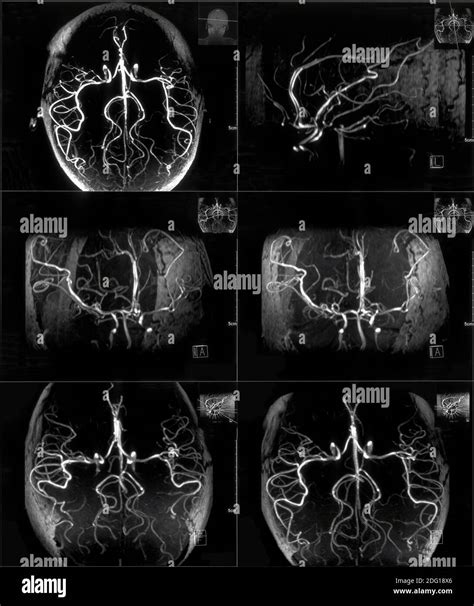

• Vascular abnormalities: Including aneurysms or arteriovenous malformations, to better visualize blood flow.

• mri brain with contrast images